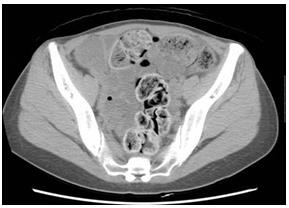

照片2:普通CT 照片

腹部全体发白。由于1.5L肠道准备药物停滞肠内,无法看见肝下缘,肾阴影,肠腰筋。看似腹水。横结肠中有少量气体。盆腔正中存在硬便和裂缝状气体。

照片4:腹部CT 照片,轴向图像,盆腔

盆腔左边的降结肠中含气体,看似软便。腹壁中间为乙状结肠,发白,水分较少,犹如石块。仙骨前面的直肠存在类似兔子粪便样的小结石状粪便。